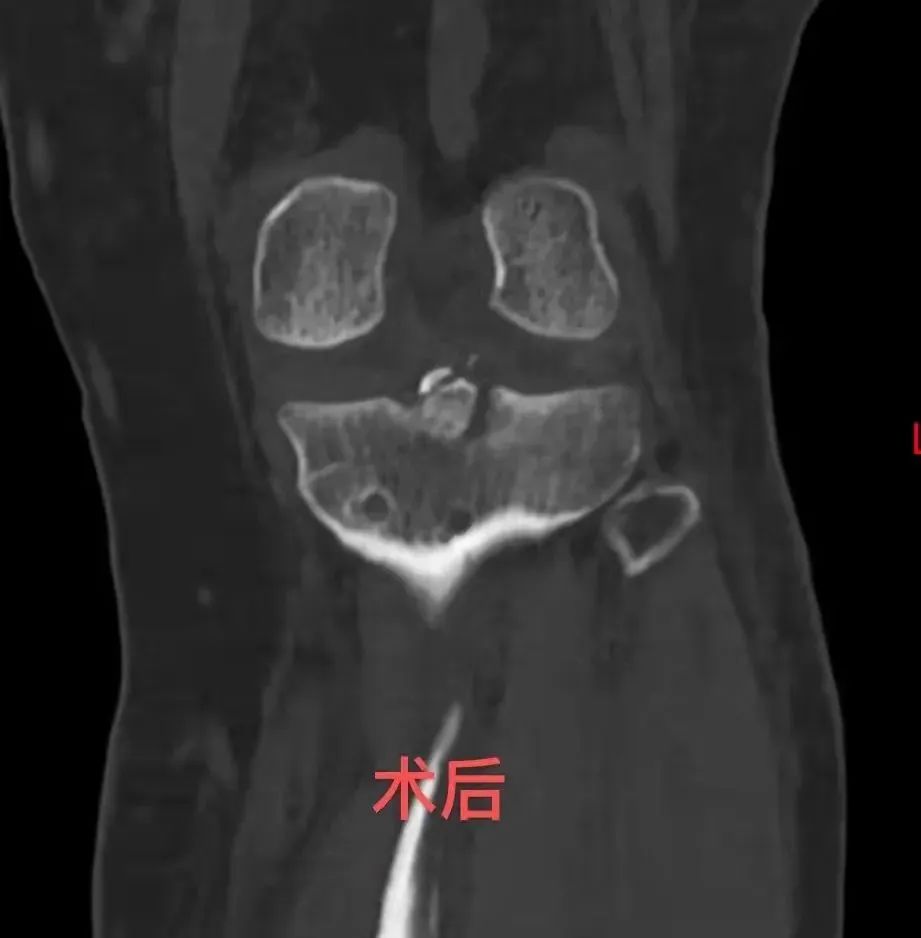

小文左腿韧带损伤严重

3组已经失效

合并关节内

粉碎性骨折

半月板完全

撕裂并移位

筋和骨都有问题!

这次,刘德鼎实现了

筋骨并重

用一次手术

解决了关节内所有病损